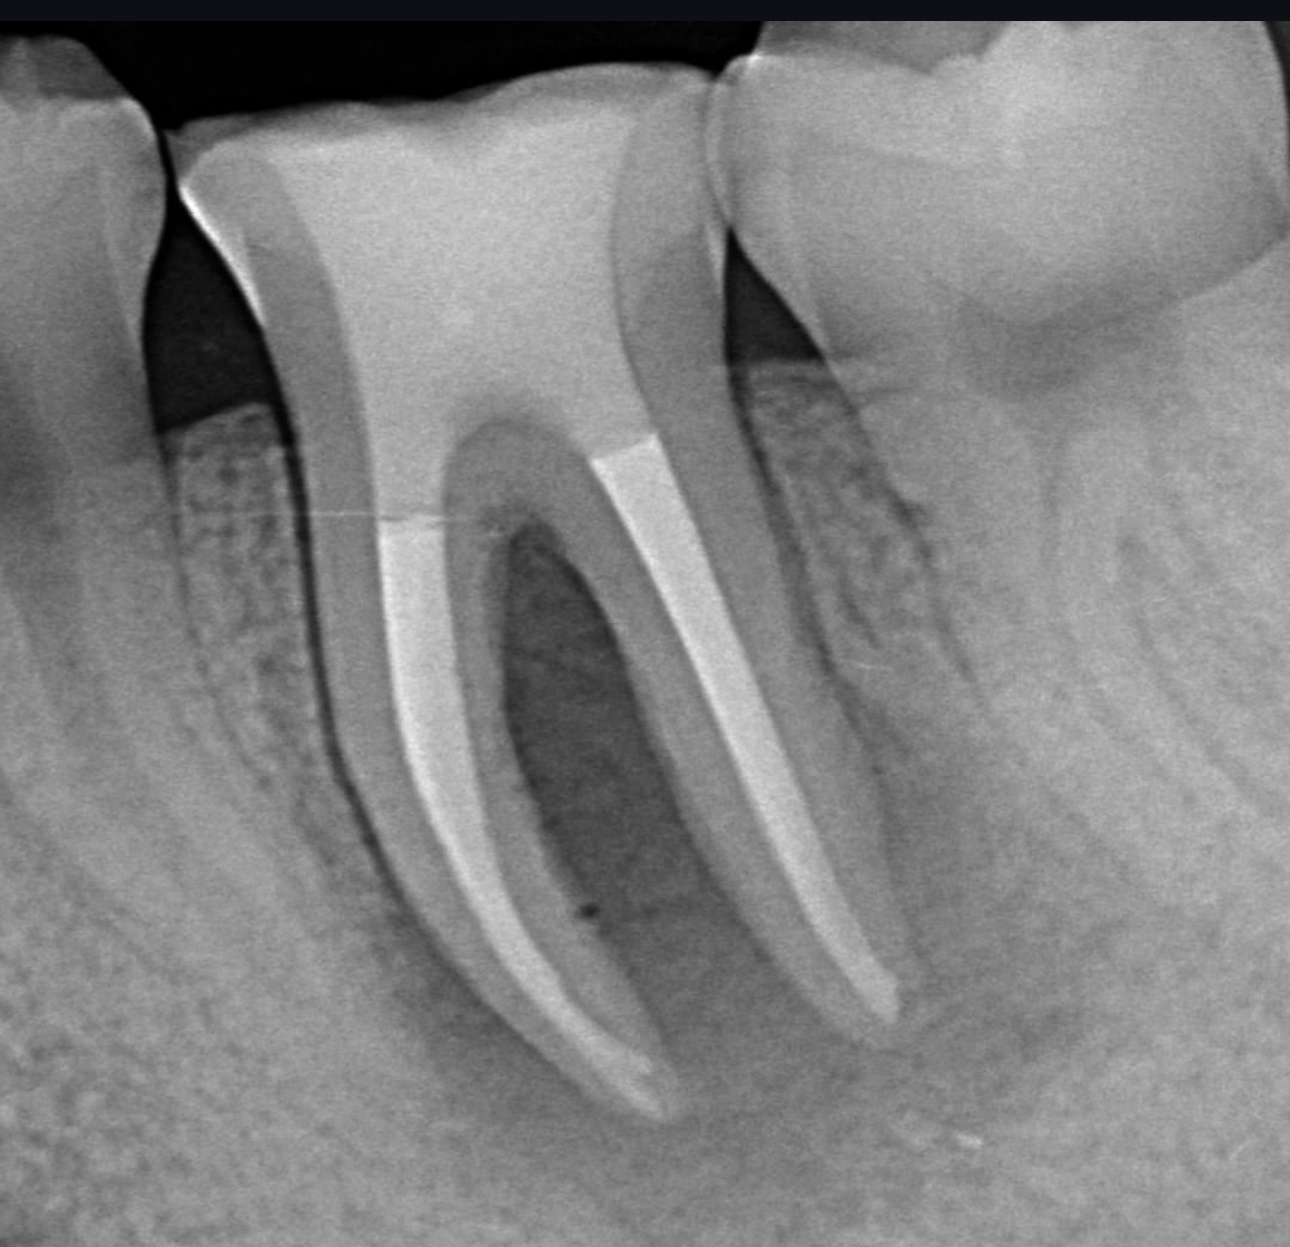

術前ですが左下6に大きな病変を認め膿がたまり抜歯が必要であるといわれ当院にお見えになりました。

根管治療術後2年です。膿の袋は綺麗に消失し被せ物が入り特に問題のない状態です。

費用 | 100000円 |

治療期間 | 6か月 |

注意事項(リスク・副作用など) | 治療の刺激や薬剤の刺激により、治療後数時間から数日後に痛みや腫れが生じる場合があります。 |

カテゴリ | 歯内療法 |